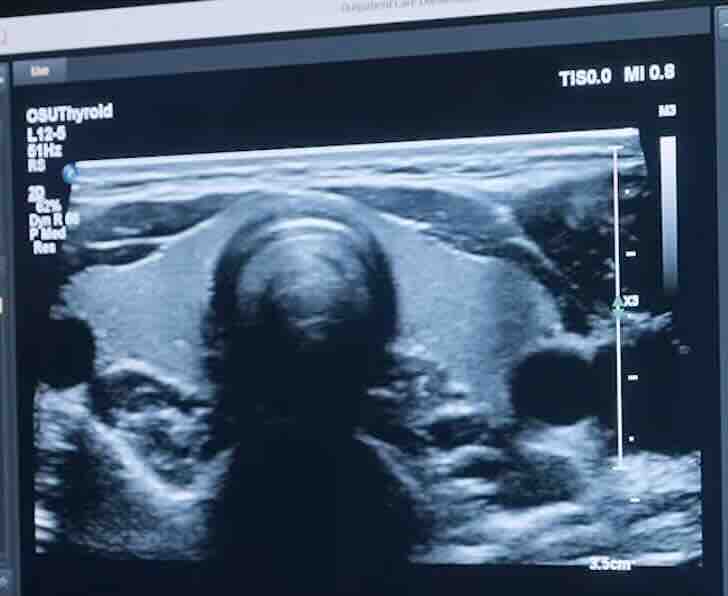

Polip/miyom varsa HSG’de çıkar mı?

HSG rahim içi boşluğun şeklini gösterir ve polip/miyom şüphesi oluşturabilir. Ancak kesin tanı için çoğu zaman ultrason, SIS (salin sonohisterografi) veya histeroskopi daha net bilgi verir. -

Rahim içi perde (septum) HSG’de belli olur mu?

HSG’de rahim iç boşluk şekli değiştiği için perde şüphesi görülebilir. Ancak tanıyı netleştirmek için 3D ultrason, MRI veya histeroskopi gerekebilir. Tedavi planı bu doğrulamaya göre yapılır. -